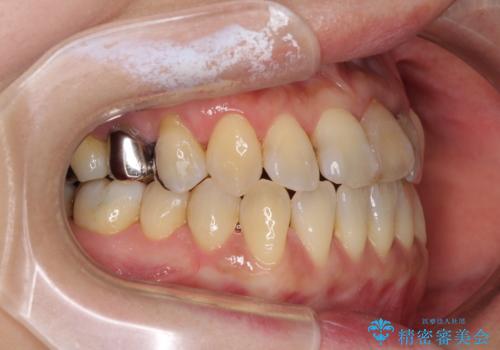

反対咬合で痛む前歯を改善 インビザラインによる矯正治療

- 前歯の反対咬合により、日々強い痛みを感じているとのことで来院された患者様です。

骨格的に下顎が前方位にありますが、歯列矯正で前歯の被蓋関係を改善することができると判断されたため、インビザラインにより矯正治療を行うこととしました。

また、上顎前歯と下顎大臼歯に神経を取り除いた歯があったため、矯正治療後に、セラミッククラウンにて補綴することとしました。

前歯が内側に倒れ込む力がかかり、正常な歯ぎしりもできないため、非常に負担のかかりやすい咬み合わせでした。

矯正治療中に上顎前歯が下顎前歯を乗り越える際は、前歯でしか咬めない状況が続くため、食事など不便を感じましたが、治療後には前歯の痛みもなくなり、安定した咬み合わせとなりました。